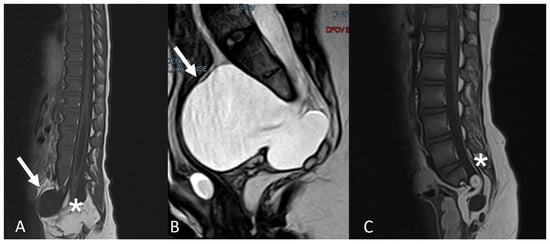

Currarino syndrome is characterised by a triad: anal malformation, presacral mass and dysgenesis (or agenesis) of the sacrum. In the case of an associated LFT or conus lipoma, a tethered cord may be present [11]. The presacral mass is, in most cases, a meningocele (Figure 3), but can also represent a teratoma [10]. In the absence of a tethered cord, a conservative approach may be considered if the radiological diagnosis of a presacral meningocele is clear and there is no suspicion of a presacral teratoma.

Figure 3. Two patients with Currarino syndrome, characterised by a presacral mass, which is most often represented by a meningocele (A,B) (white arrows). The spinal cord can be tethered by a conus lipoma (A) or by a LFT (C) (asterisks).